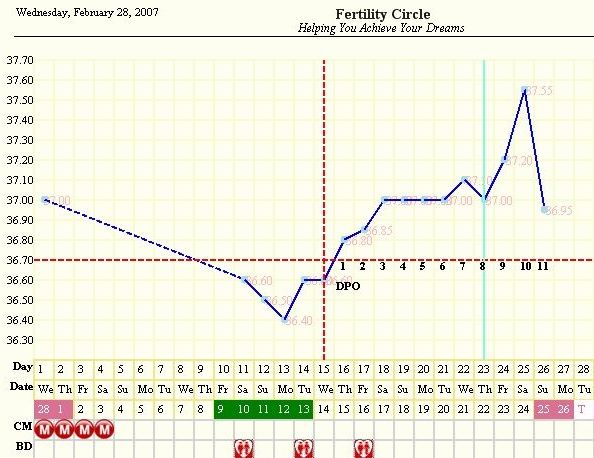

Gaby, hát ez nagyon ígéretes

, ha holnap megint felugrik én már nem mondok semmit, úgyis tudni fogod mire gondolok